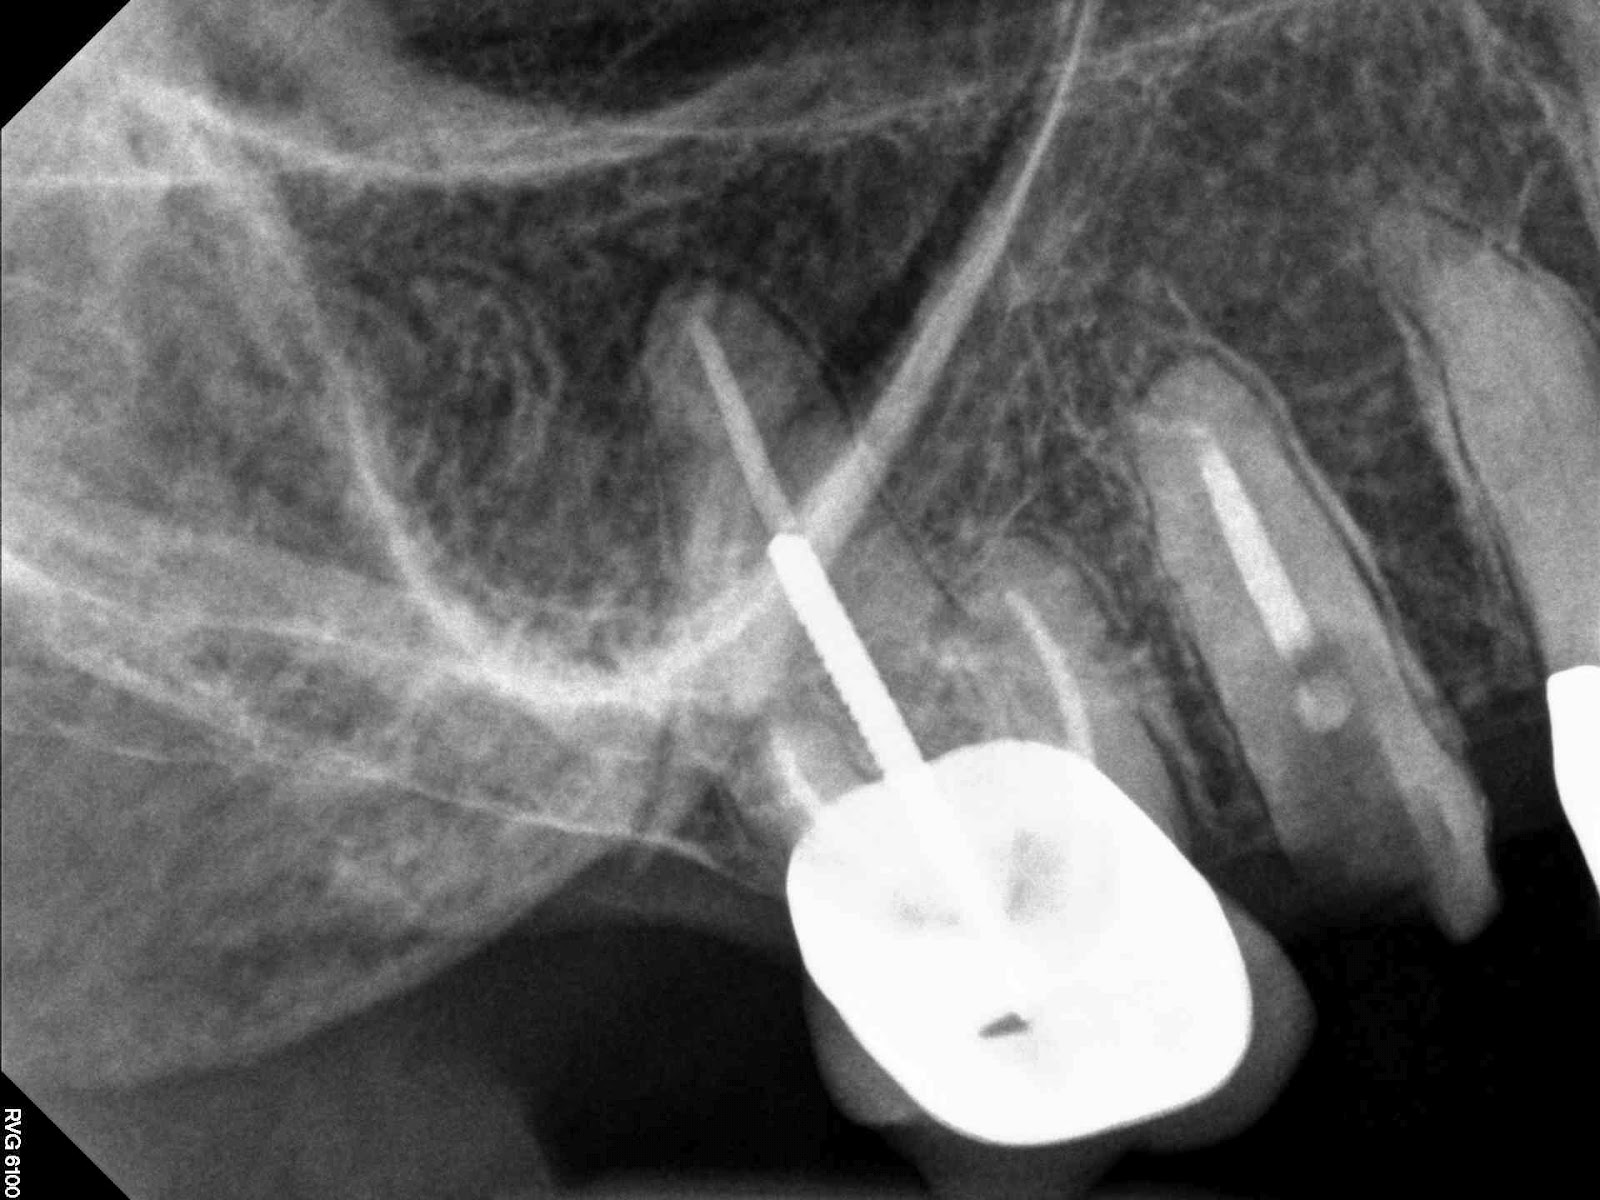

| Slight mesial angulation to avoid sinus |

| Final. maybe could have gone with the 16mm with die back probably would end up about 1mm higher than will now. |

| Will need custom abutment |